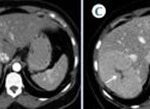

Colangiocarcinoma

El colangiocarcinoma es una neoplasia maligna originada en el epitelio de las vías biliares. Representa el segundo tumor más frecuente del sistema hepatobiliar, por detrás del carcinoma hepatocelular. La mayoría son adenocarcinomas independientes de su localización en el hígado.

El Liver Cancer Study Group of Japan, en 2009, propuso una clasificación basada en el patrón de crecimiento tumoral, que es muy útil para el diagnóstico por imagen, ya que describe la apariencia macroscópica de la infiltración y de esta manera se complementa con los hallazgos encontrados en las pruebas de imágenes permitiendo realizar un diagnóstico diferencial. Clasifica los tumores en tres grupos: los formadores de masa, los de infiltración predominantemente periductal (Anexo 16) y los de crecimiento intraductal. Existe predominio de un patrón de crecimiento u otro en función de la localización topográfica: el colangiocarcinoma intrahepático suele debutar como una masa, mientras que en los colangiocarcinomas hiliar y extrahepático predomina la infiltración periductal.

El reforzamiento en anillo (hipercaptación periférica) o incluso menos de 25% de la lesión, y es más frecuente en nódulos mayores a 3 cm. En la fase venosa portal puede permanecer invariable cuando los nódulos son pequeños. Puede presentar un reforzamiento progresivo: existiendo el máximo realce en fases tardías (más frecuentes en nódulos de mayor tamaño). También puede demostrar un reforzamiento continuo con área central que no capta el medio de contraste. En la fase tardía la región central puede mostrar un reforzamiento variable en función de la existencia de fibrosis (aumento de la captación) o necrosis coagulativa (sin captación del contraste).(18-22)